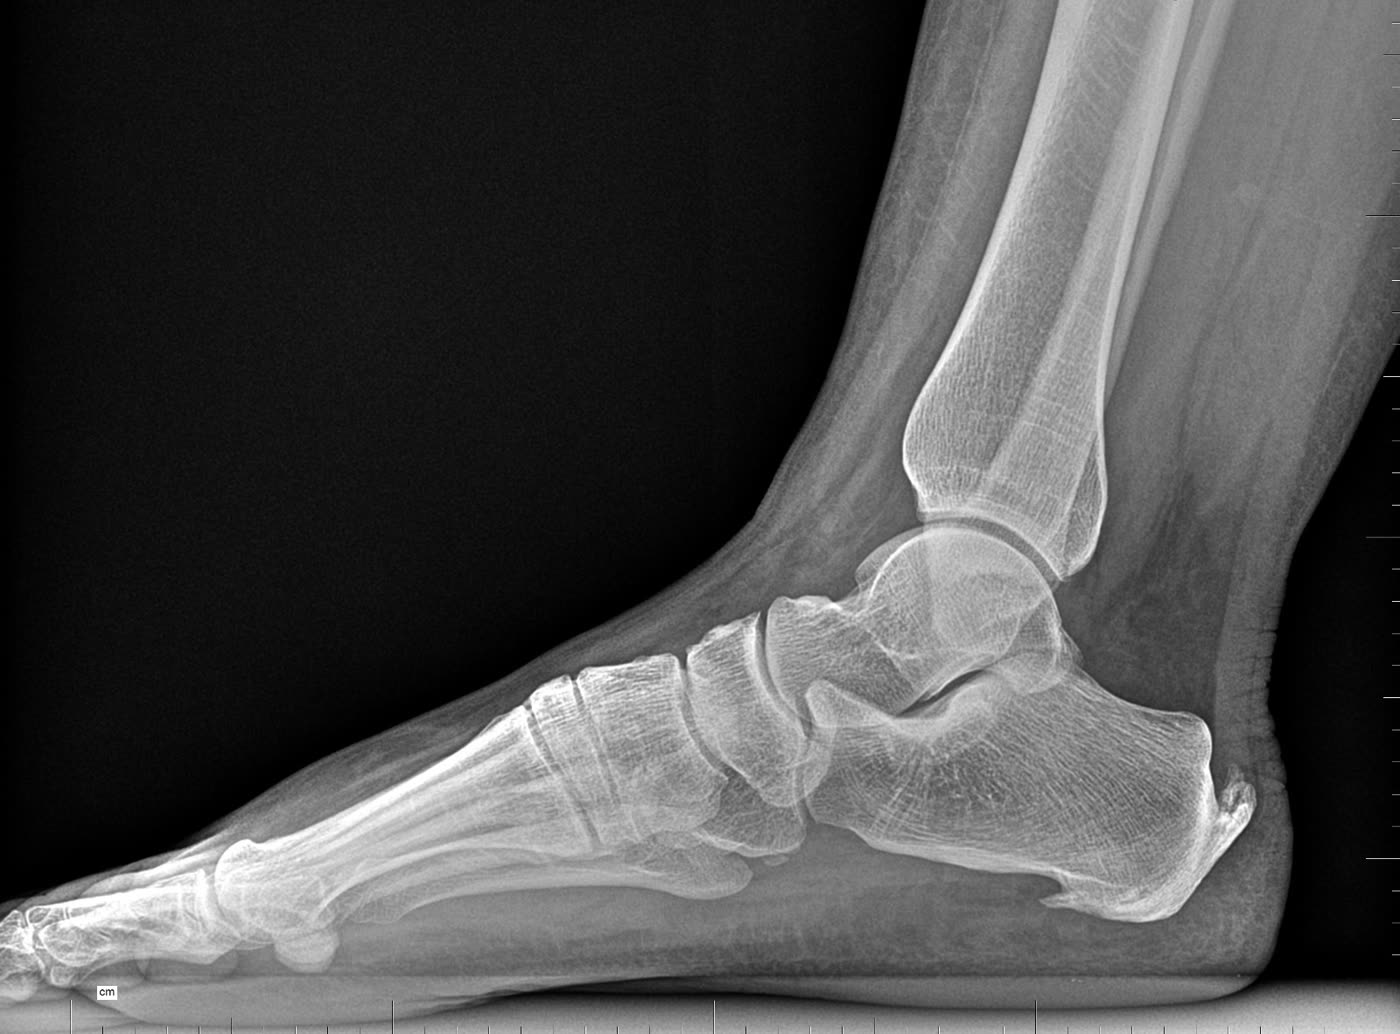

Radiología digital

Disponemos de radiología digital en consulta para el estudio de la estructura ósea del pie y tobillo. Imprescindible en el diagnóstico de fracturas, deformidades como el hallux valgus (juanete), pie plano o cavo estructural, artritis, etc. Las imágenes son inmediatas, de alta resolución y con mínima radiación.

Hallux valgus Fracturas Artritis Deformidades

Radiografía pie — proyección lateral Radiografía pie — proyección dorso-plantar

Arrastra para comparar · Radiología digital en consulta